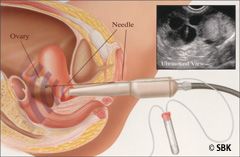

Paso 3: Extracción del Huevo: El doctor aspira cada folículo maduro con una aguja guiada por ultrasonido. El procedimiento se lleva con sedación administrada por un anestesiólogo matriculado y en una sala especial de extracción de huevos con filtración de aire. Esto generalmente se realiza a través de la parte posterior de la pared vaginal pero en ocasiones raras, puede llevarse a cabo por el abdomen. Los huevos aspirados luego se transfieren al embriólogo para que realice la identificación y fertilización.

Paso 3: Extracción del Huevo: El doctor aspira cada folículo maduro con una aguja guiada por ultrasonido. El procedimiento se lleva con sedación administrada por un anestesiólogo matriculado y en una sala especial de extracción de huevos con filtración de aire. Esto generalmente se realiza a través de la parte posterior de la pared vaginal pero en ocasiones raras, puede llevarse a cabo por el abdomen. Los huevos aspirados luego se transfieren al embriólogo para que realice la identificación y fertilización.